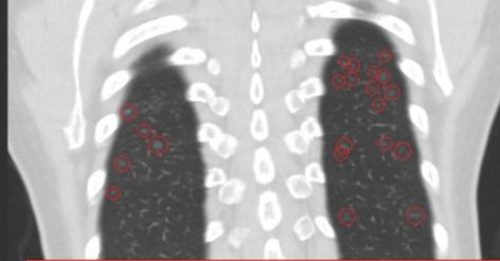

60岁女满天星肺结节 医生急劝快换工作